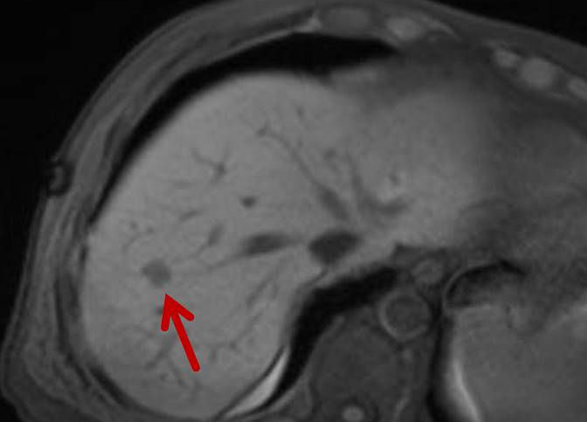

Das Osteoidosteom ist ein gutartiger, jedoch sehr schmerzhafter Knochentumor, der bevorzugt bei jüngeren Patienten auftritt. Die Radiofrequenzablation (RFA) hat sich in den letzten Jahren zu einer zuverlässigen, minimalinvasiven Therapieoption bei der Behandlung des Osteoidosteoms entwickelt und wird seit über 15 Jahren an der Uniklinik Tübingen angewandt.

Abbildung: Osteoidosteom (Pfeil) im Schienbein bei einem jungen Patienten. Unter CT-Bildgebung wird ein spezieller Applikatoren unter CT-Bildgebung in das Osteoidosteom eingebracht. Durch Hitze wird dieses effektiv und dauerhaft zerstört.